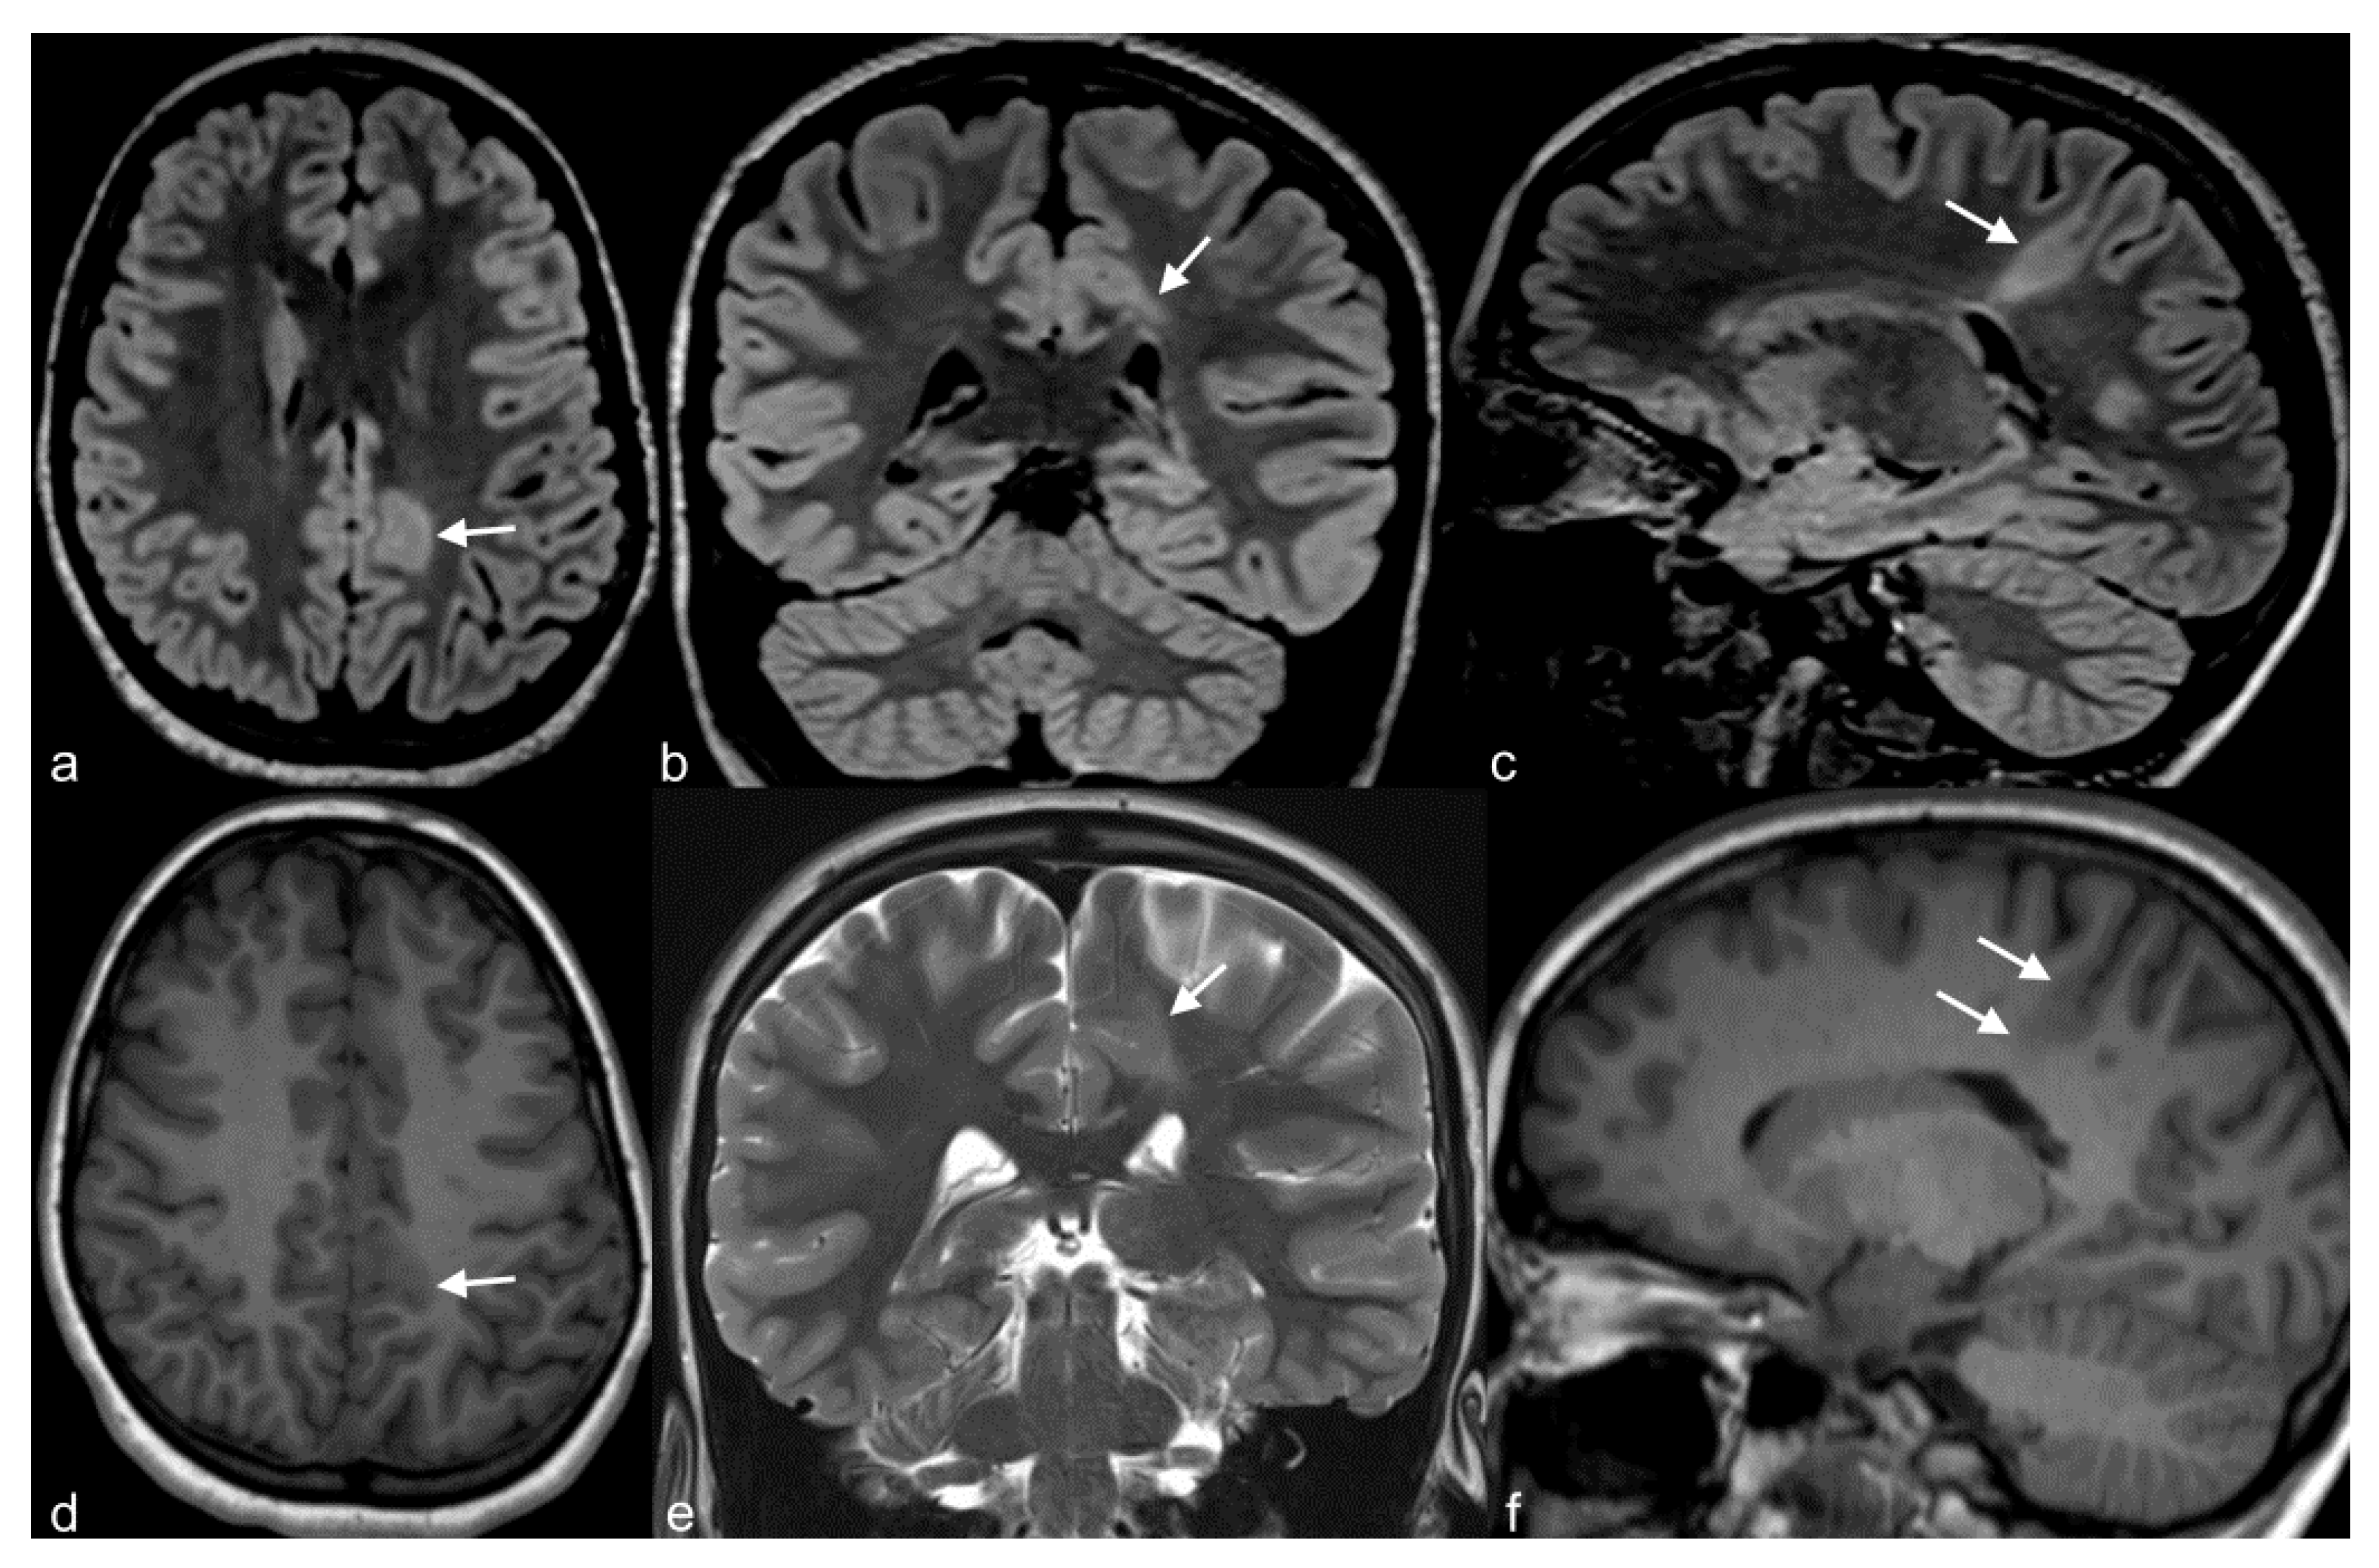

4.2. Focal Cortical Dysplasia

Focal cortical dysplasia (FCD) is probably the most common cause of refractory extratemporal focal epilepsy, especially in the pediatric population [75]. Epilepsy due to FCD commonly begins in the first few years of life and may occur shortly after birth [75]. The term “focal cortical dysplasia” was introduced by Taylor et al. [76] in order to describe a malformation of cortical development in the human brain that consisted of disorganized cortex with enlarged dysplastic neurons and enlarged balloon cells. This type of FCD is nowadays classified as FCD type II; type I FCD is also characterized by abnormal cortex with distorted architecture, but individual neurons are normal and not enlarged as in type II [77]. A type III FCD has recently been described, but it is not generally considered a distinct entity in itself; it is FCD I or II associated with another primary lesion, such as HS, tumor, vascular malformation, ischemic scars, or other [78]. FCD type II is characterized by focal cortical thickening, “blurring” of gray/white matter interface, subcortical T2/FLAIR hyperintensity and sometimes a funnel-shaped high T2/FLAIR signal pointing towards the ventricles (“transmantle sign”) (Figure 5) [76,77,78], while findings in FCD type I are usually subtler and this latter is usually more difficult to detect. FCD has a predilection for the frontal lobes, contrary to HS and epileptogenic tumors, usually located in the temporal lobes. FCD represents a great part of “nonlesional” MRIs in patients with medically refractory epilepsy, due to its small size or subtle architectural changes, undetected by neuroimaging techniques. For this reason, multiplanar reconstruction of high-resolution images, as well as advanced methods such as DTI and spectroscopy are important for detection and confirmation of subtle lesions, especially when these are located at the bottom of the sulcus. DTI shows decreased connectivity in the area around the dysplastic cortex and spectroscopy shows decreased NAA/Cr ratio. These techniques or metabolic imaging (PET-CT and SPECT imaging) may highlight suspicious cortical areas, that can be re-inspected on initial MR images [23,79] and increase lesion detection this way. Complete resection of FCD is the best predictor for seizure control [23,42] and for this reason surgical treatment has better outcomes for FCD type II compared to type I. Presurgical detection of the epileptogenic focus is therefore of the utmost importance. Close correlation of semiology, EEG, MRI with advanced techniques and/or ultra-high field, as well as PET-CT/SPECT findings, is required in order to improve prognosis not only for seizure control of these patients, but also for the developmental outcome in the pediatric population suffering from epilepsy due to FCD treated by surgery at early stages [23,80,81].

Figure 5.

10-year-old girl with cortical dysplasia. There is thickening of the cortex on the left mesial fronto-parietal region (arrows in (a) to (f)) associated to funnel-shaped hyperintensity of the surrounding white matter (arrows in (b,e)). Note blurring between the white and gray matter interface (f).